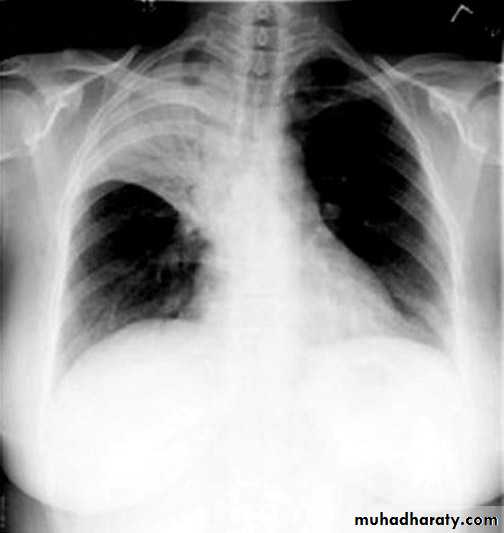

Total collapse total consolidation

Total collapse

48.opasified hemi thorax

49.total collapse

50.pleural effusion